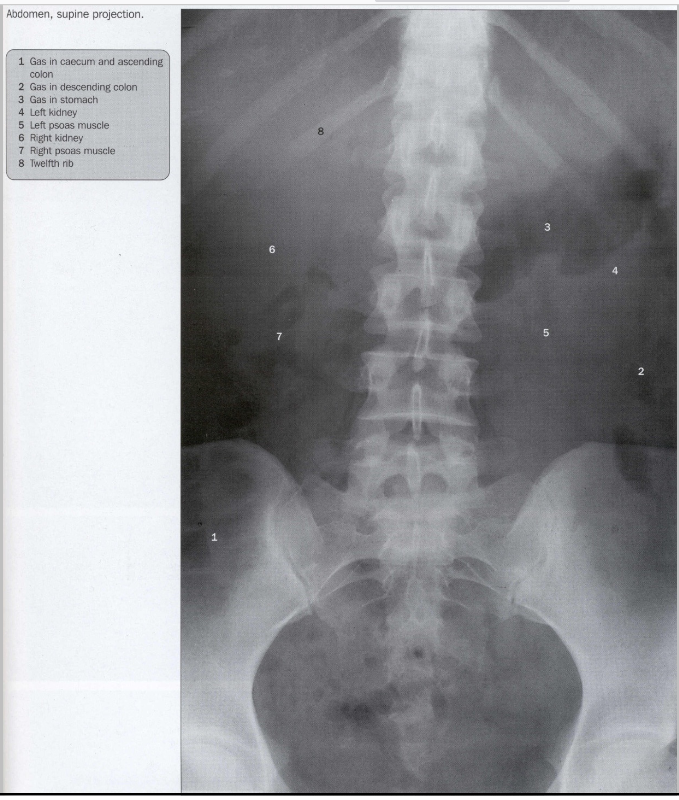

FOTO 1: staande patiënt

FOTO 2: liggende patiënt

curvatura minor

curvatura major

grens tussen gas-vocht

rechter hypochondrium

→ daar zit lever (dus geen gas te zien)

nieren

→ hoe dikker de patiënt, hoe beter te zien (want meer vet rond nieren)

colon ascendens

caecum

ileum

os ilium

(linker hypochondrium)